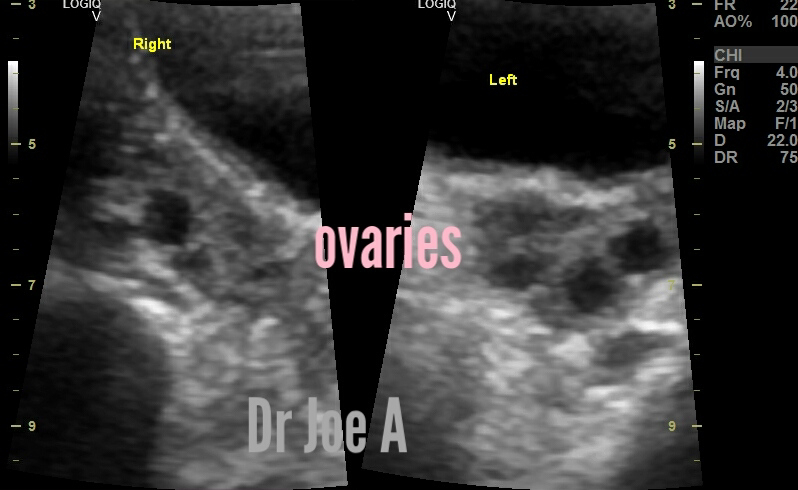

ultrasound findings:

for PCOD in this 30-year-old female with ovaries of 11 cc volume each include:

The Rotterdam consensus defined the polycystic ovary as having 12 or more follicles, measuring between 2 and 9 mm (FNPO), and/or an ovarian volume (OV) >10 cm.

Ovary size and volume is frequently determined with ultrasound. The normal, adult, non-pregnant, mean ovary volume of women who are not postmenopausal is 6-7 mL.

Thus this patient has an ovarian volume of 11 cc each.

Final diagnosis: PCOD